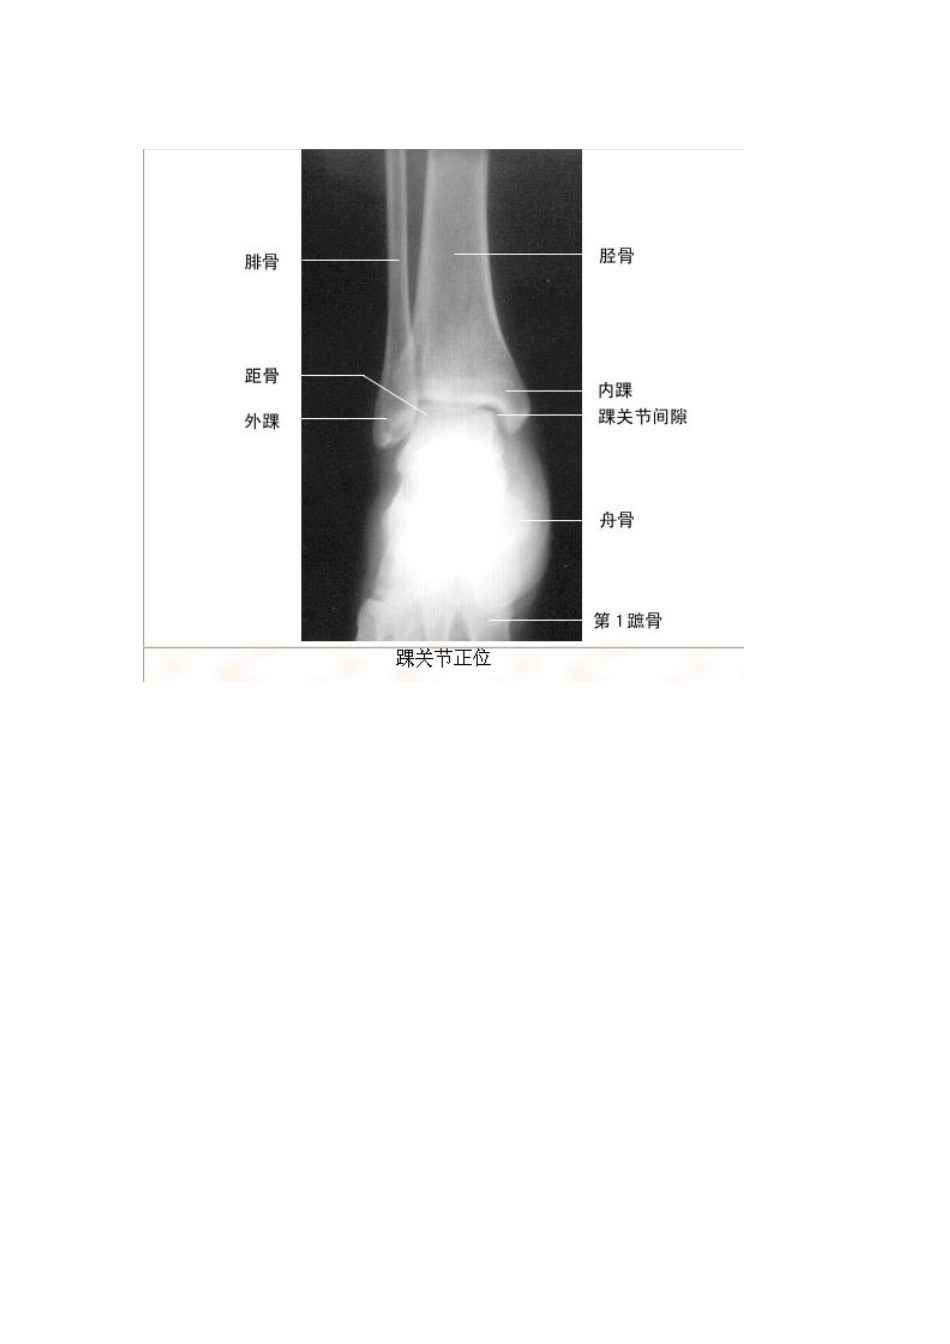

影像解剖珍藏版VIP免费